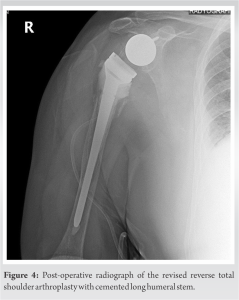

Further evaluation was done with a computed tomography of the right shoulder to evaluate any occult fracture around the shoulder girdle and bony fracture was excluded from the study. A one-stage operation was planned for revision. We used the previous incision line for the deltopectoral approach. After reaching the glenohumeral joint, the prosthesis was found to be dislocated and broken at the humeral tray of proximal stem. The model itself was a modular stem and due to the suspicion of infection, samples were taken from the surrounding synovium and joint fluid. Metallosis and debris tissue were debrided. The humeral stem and the glenoid hemisphere were removed with its cement (Fig. 2 and 3) and a cemented long humeral stem (SMR, Lima LTO, Udine, Italy) was placed (Fig. 4).

The glenohumeral joint was then reduced and the layers were anatomically closed. No post-operative complications were spotted. The synovial culture which had been taken for the suspicion of an infection was reported sterile. A frozen section analysis revealed active chronic synovitis, fibrosis, and giant cell reaction of foreign bodies. Shoulder physiotherapy with ROM and strengthening exercises were applied to the patient for 3-month postoperatively. No complication has occurred during his 3-year follow-up after surgery and the patient has nearly full ROM with only 20° of loss in abduction and has neither pain nor complaints. The patient was satisfied with result of the treatment and gained full function of his right shoulder.